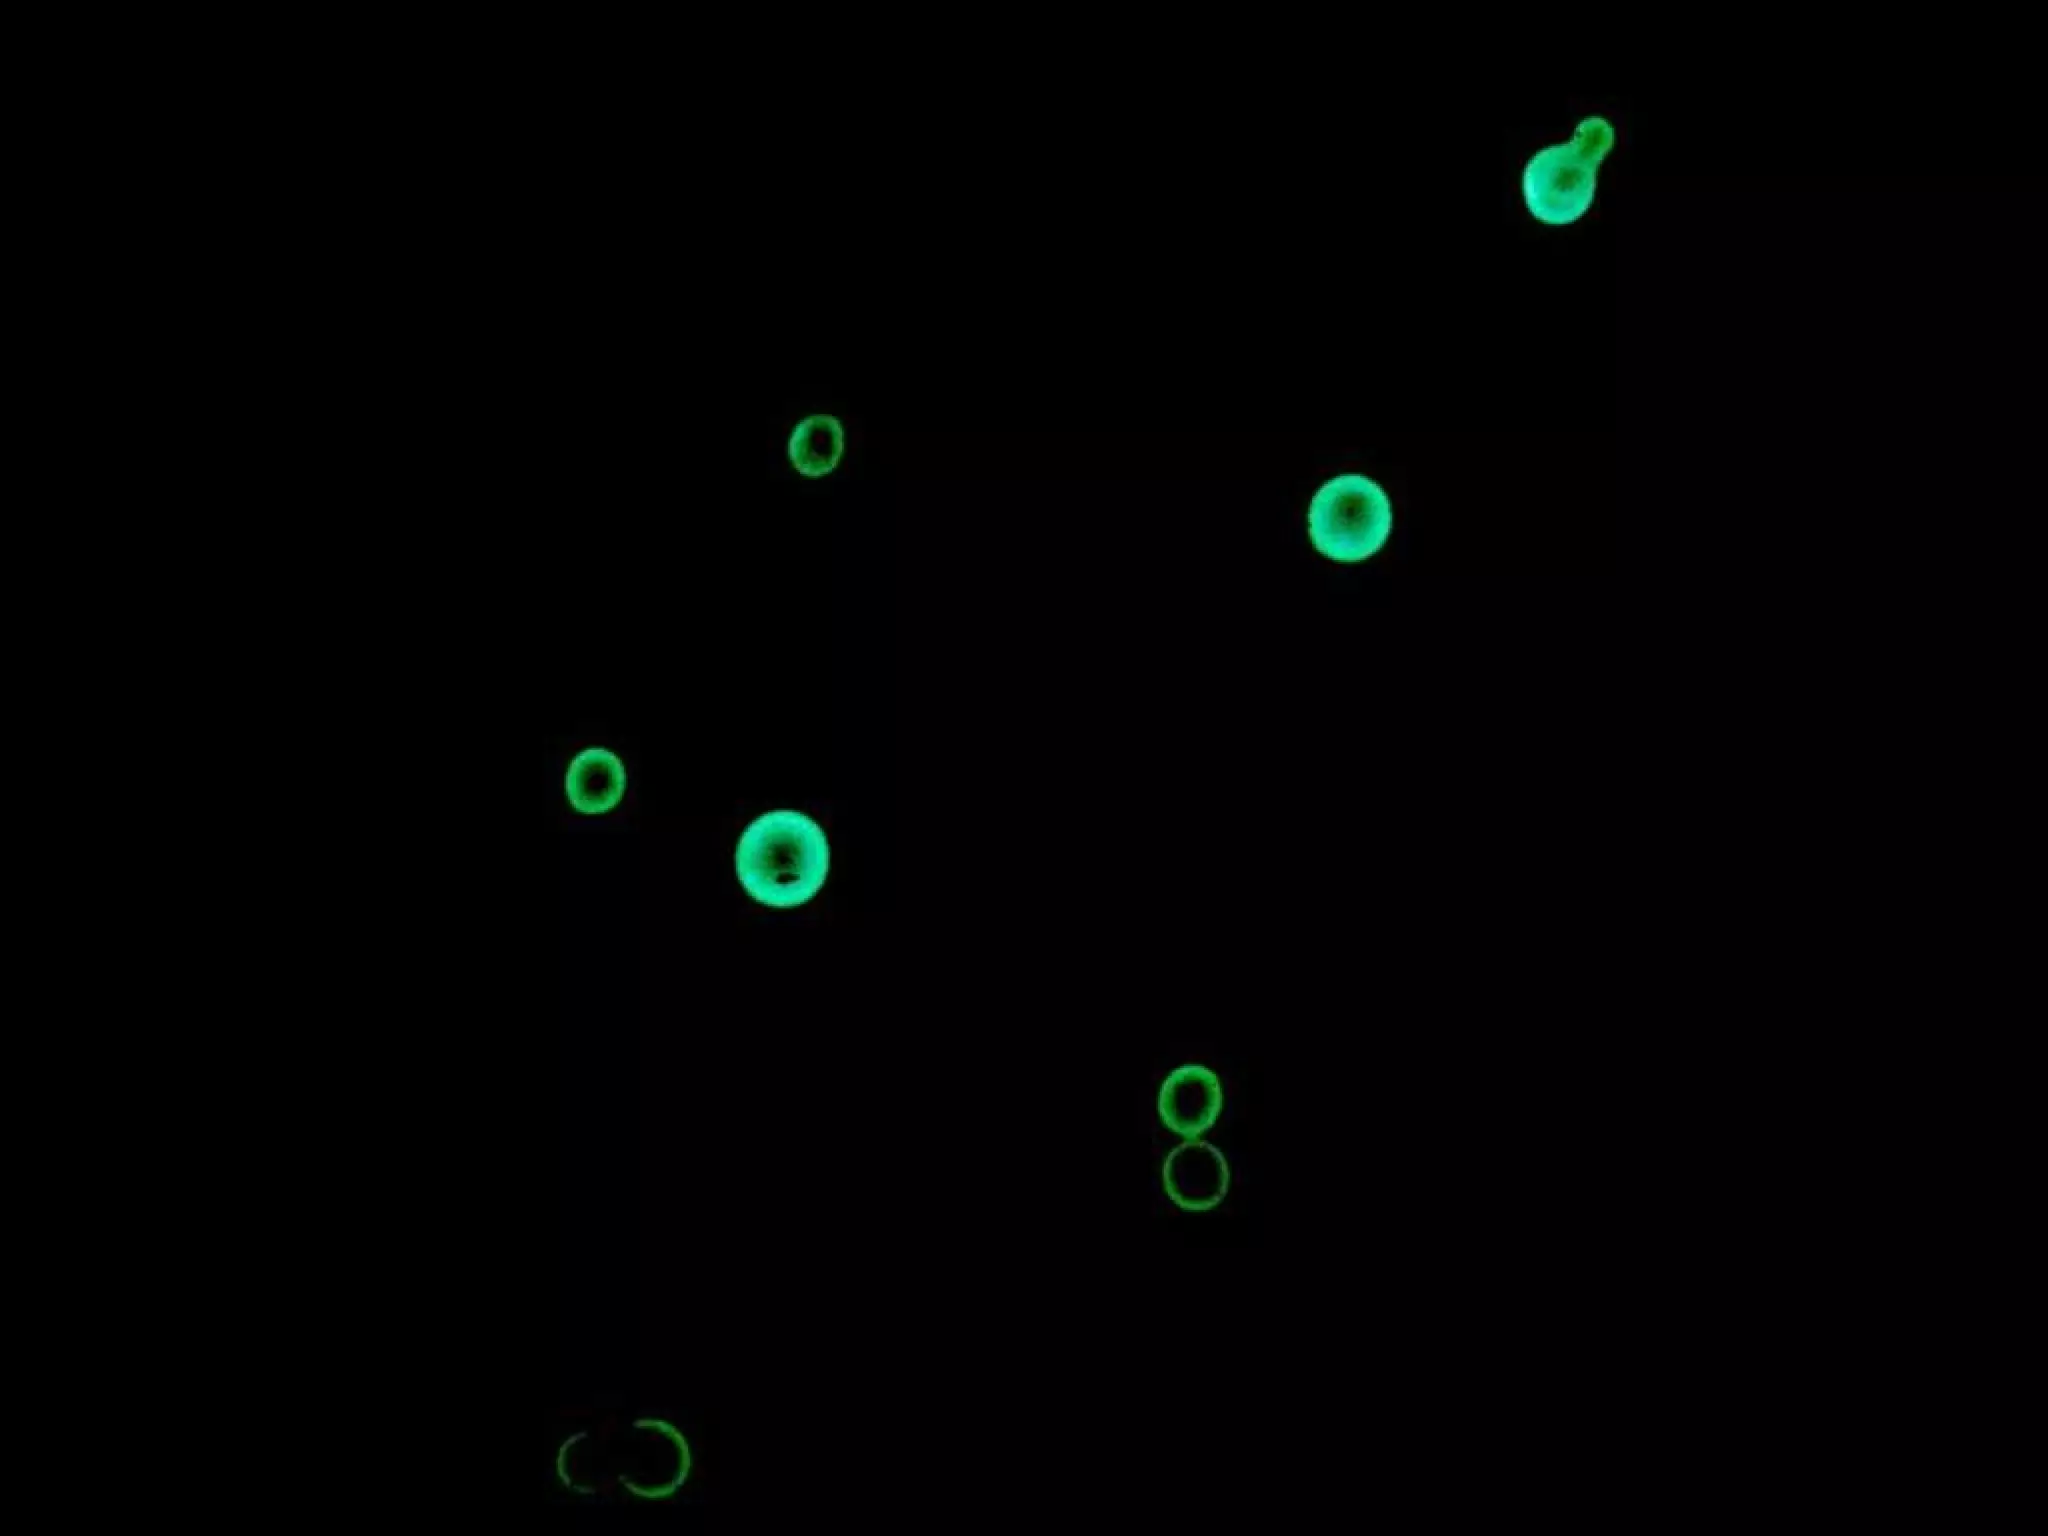

• Unicellular fungi

• Fission yeasts divide symmetrically

• Budding yeasts divide asymmetrically

Saccharomyces and Candida

Yeasts

Figure 12.3

Yeast Reproduction

• FISSION

• BUDDING

• “uneven” reproduction, parent cell’s nucleus

divides and migrates to form a bud and then

breaks away